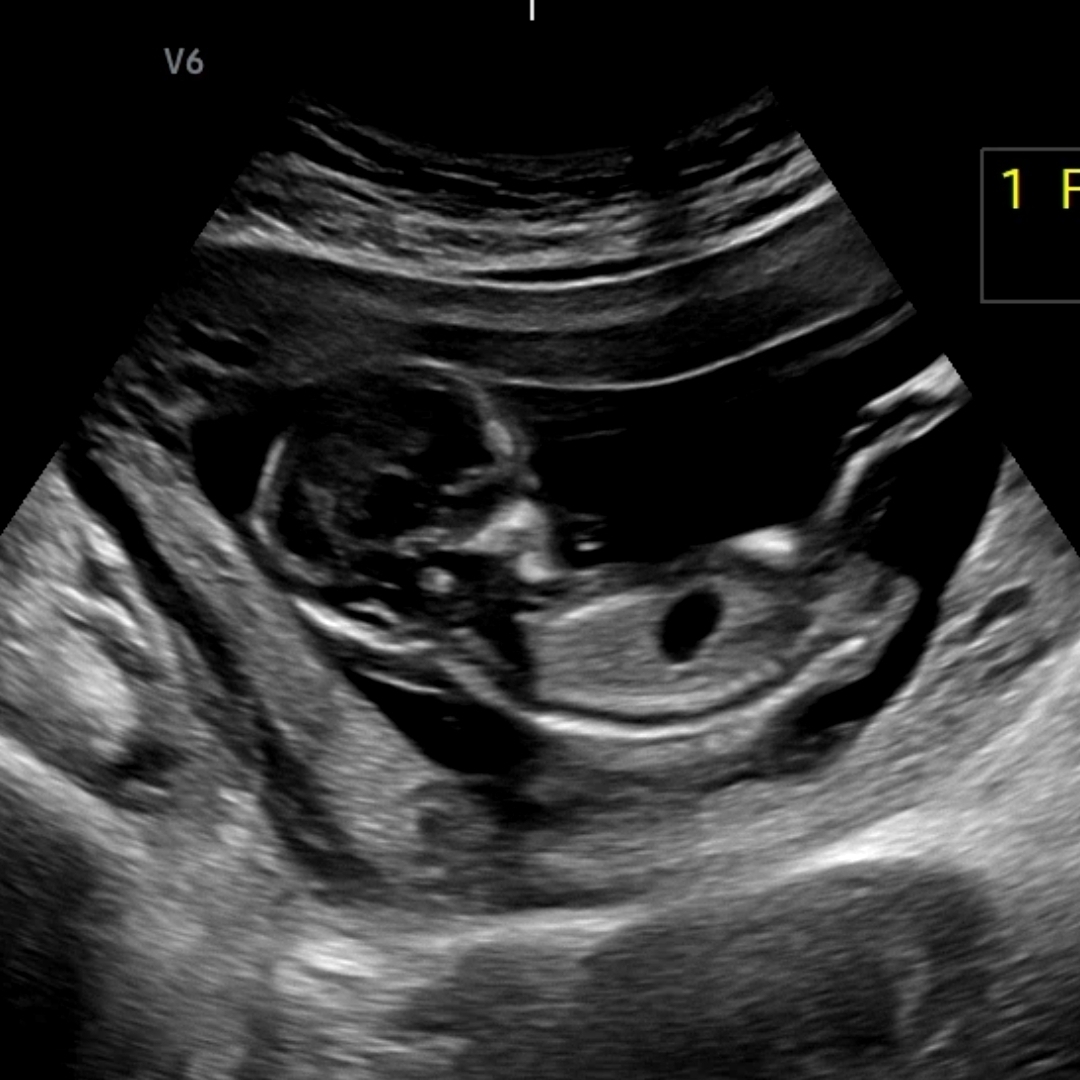

혹시 각도법 보이실까요??

넘 궁금해요!!!